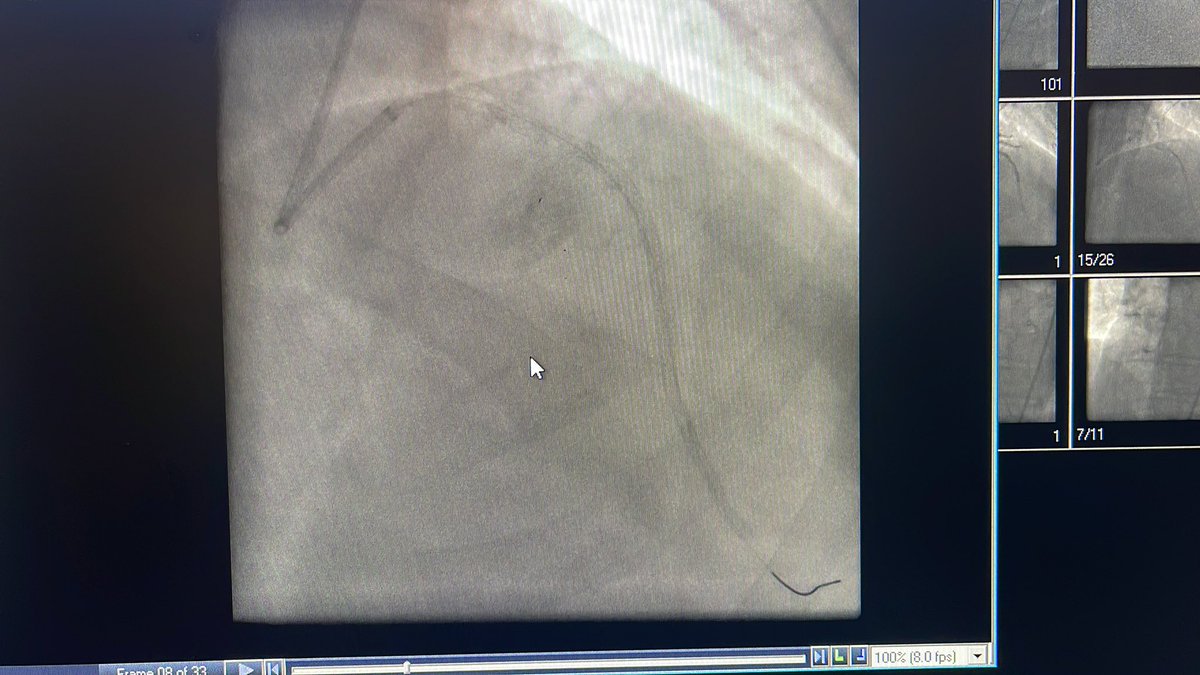

Justin Levisay@jlevismd·

@rowpower ✅Sternotomy fixation device ✅Sternotomy wire x 1 ✅Dual chamber PPM ✅Prior open MVR s/p TMVR w/ S3 ✅Temp pacer wire ✅Micra leadless ✅Bypass Clips at RCA ❌RCA DES-close, self- expanding stent in large SVG ✅ septal occluder